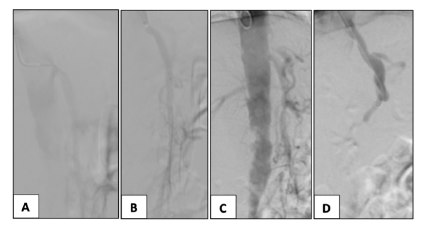

In two patients, proximal SMA stenosis was treated with proximal extension with a covered stent, Figure 2. One patient with SMA stenting stenosis was submitted to SMA angioplasty with a DCB and CT stenting with a covered stent, Figure 3. In one patient with SMA stent reocclusion, a two-vessel revascularization with aorto-mesenteric bypass and IMA re-implantation was performed due to IMA ostial high-grade stenosis and previous evidence of an incomplete right aorta’s arch. Thirty-day and 3-year overall survival in the OR and ER groups were 67% vs. 93% and 44% vs. 87%, respectively (p=.015, Figure 4).

(A) restenosis of the SMA is noted; (B) treatment with proximally extension with a covered-stent Advanta 5x38mm to SMA ostium.